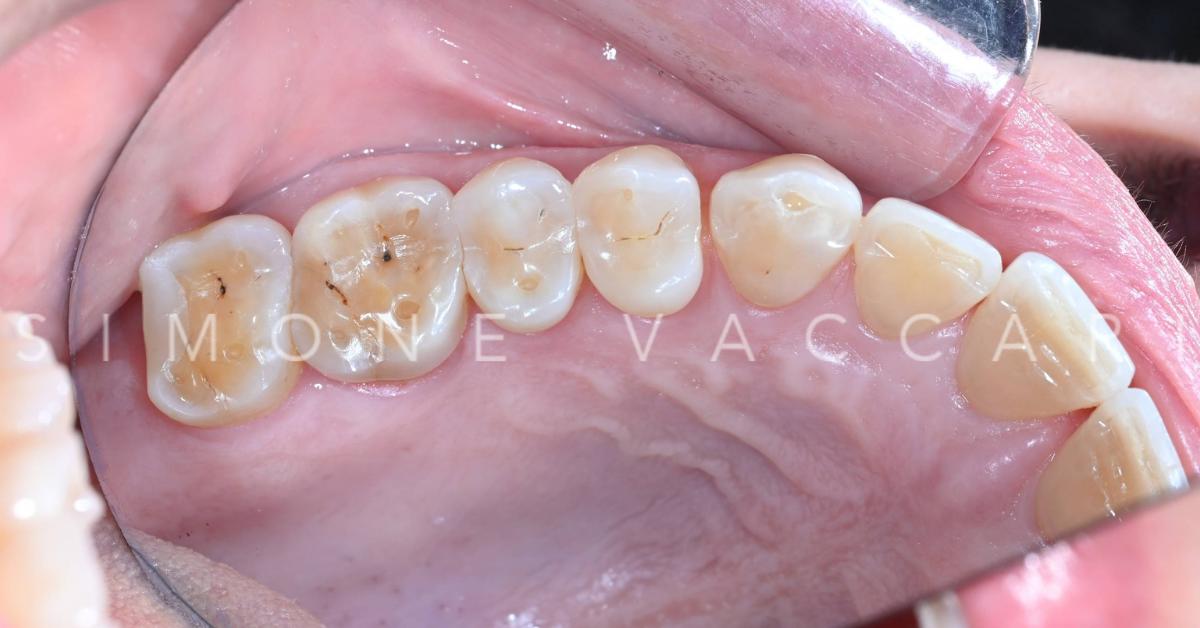

Sui due molari è presente una otturazione bianca e attorno appara ampia area di erosione

Stesso fenomeno "Restoration standing proud" da altra angolazione